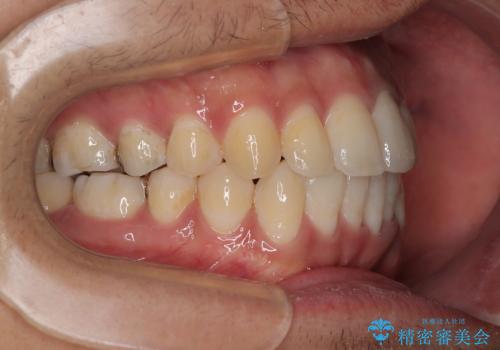

- 前歯のデコボコや八重歯を気にして来院された患者様です。

他院でワイヤー矯正を行うつもりでいらっしゃったそうですが、通院が難しくなったとのことで当院での治療を希望されて来院されました。

上下ともに歯列幅が狭く、その影響でデコボコになっていたため、ワイヤー装置を用いて歯列を側方に拡大しながら、デコボコを解消していくこととしました。